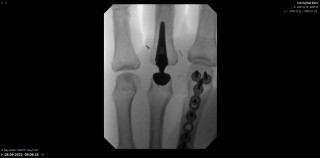

Introduction: Attritional rupture of the flexor pollicis longus (FPL) tendon has been described in cases of friction on a palmar distal radius osteosynthesis plates. We present a case of an attritional rupture of the FPL tendon by a retrograde scaphoid screw inserted two years earlier. Commonly accepted surgical therapy of attritional tendon rupture is tendon reconstruction or tendon transfer. In this particular case a primary suture was performed.

A 43-year-old high-level rock climber suffered a displaced fracture of the middle third of the scaphoid. The pre-operative ct scan revealed a bone cyst in the distal part of the scaphoid (Figure 1A). Due to this cyst, the retrograde Herbert like screw was inserted close to the palmar cortex to have the best hold in the bone (Figure 1B). Fracture healing was achieved after 6 weeks and the post-operative follow up remained unremarkable without any patient complaint. Two years later during an inverted grip in climbing (finger and thumb flexion with wrist hyperextension), the patient experienced a rupture of the FPL tendon due to palmar overhand. The palmar radiocarpal joint capsule was perforated (Figure 2). The screw protruding from the palmar surface of the scaphoid was removed. The FPL rupture was oblique and acute in appearance. Contact between the two stumps was easy and did not induce excess flexion of the thumb, which is why we opted for a direct suture and not an intercalated graft. Direct suture of the FPL tendon was performed using the Lim-Tsai technique (Supramid) and reinforced with a Krakow suture (FiberWire).